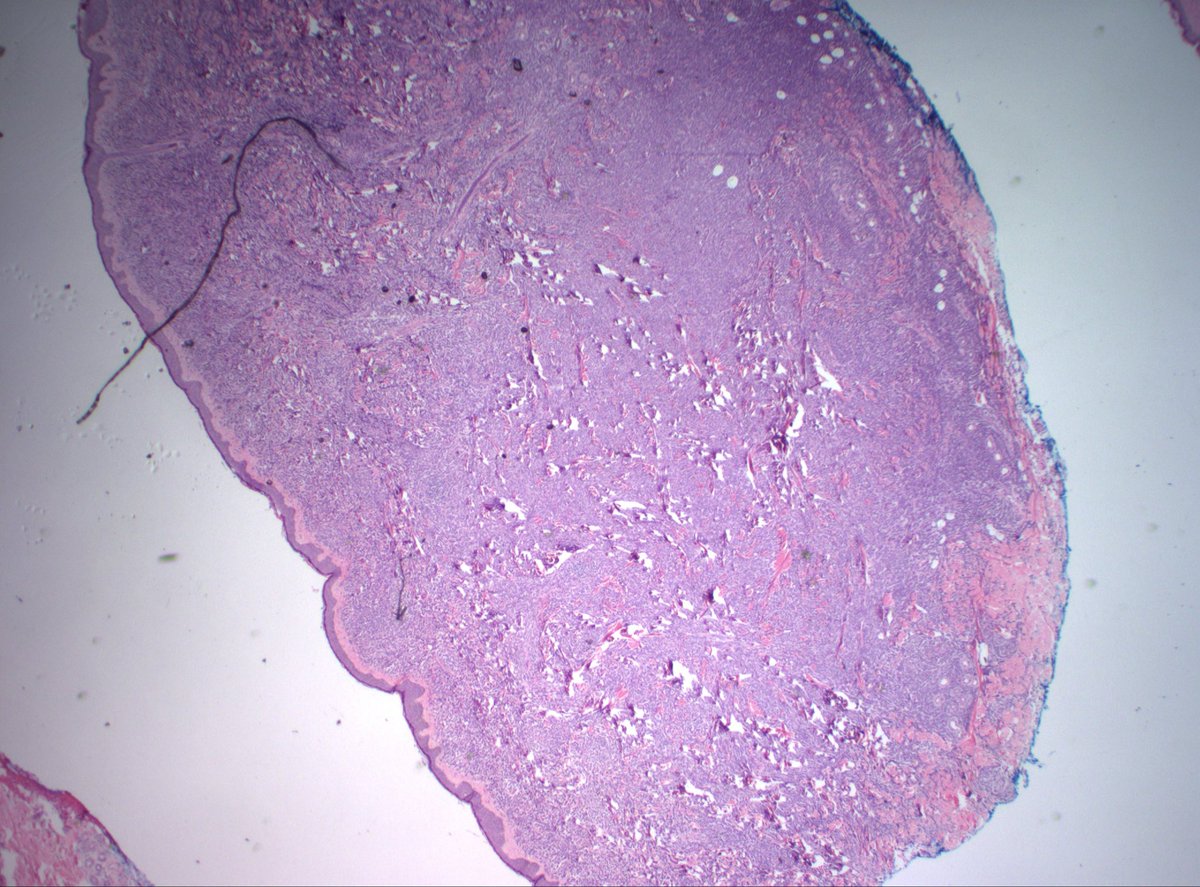

@MirunaPopescu13

DLBCL, NOS showing signet ring cell-like morphology. #hemepath #PathTwitter